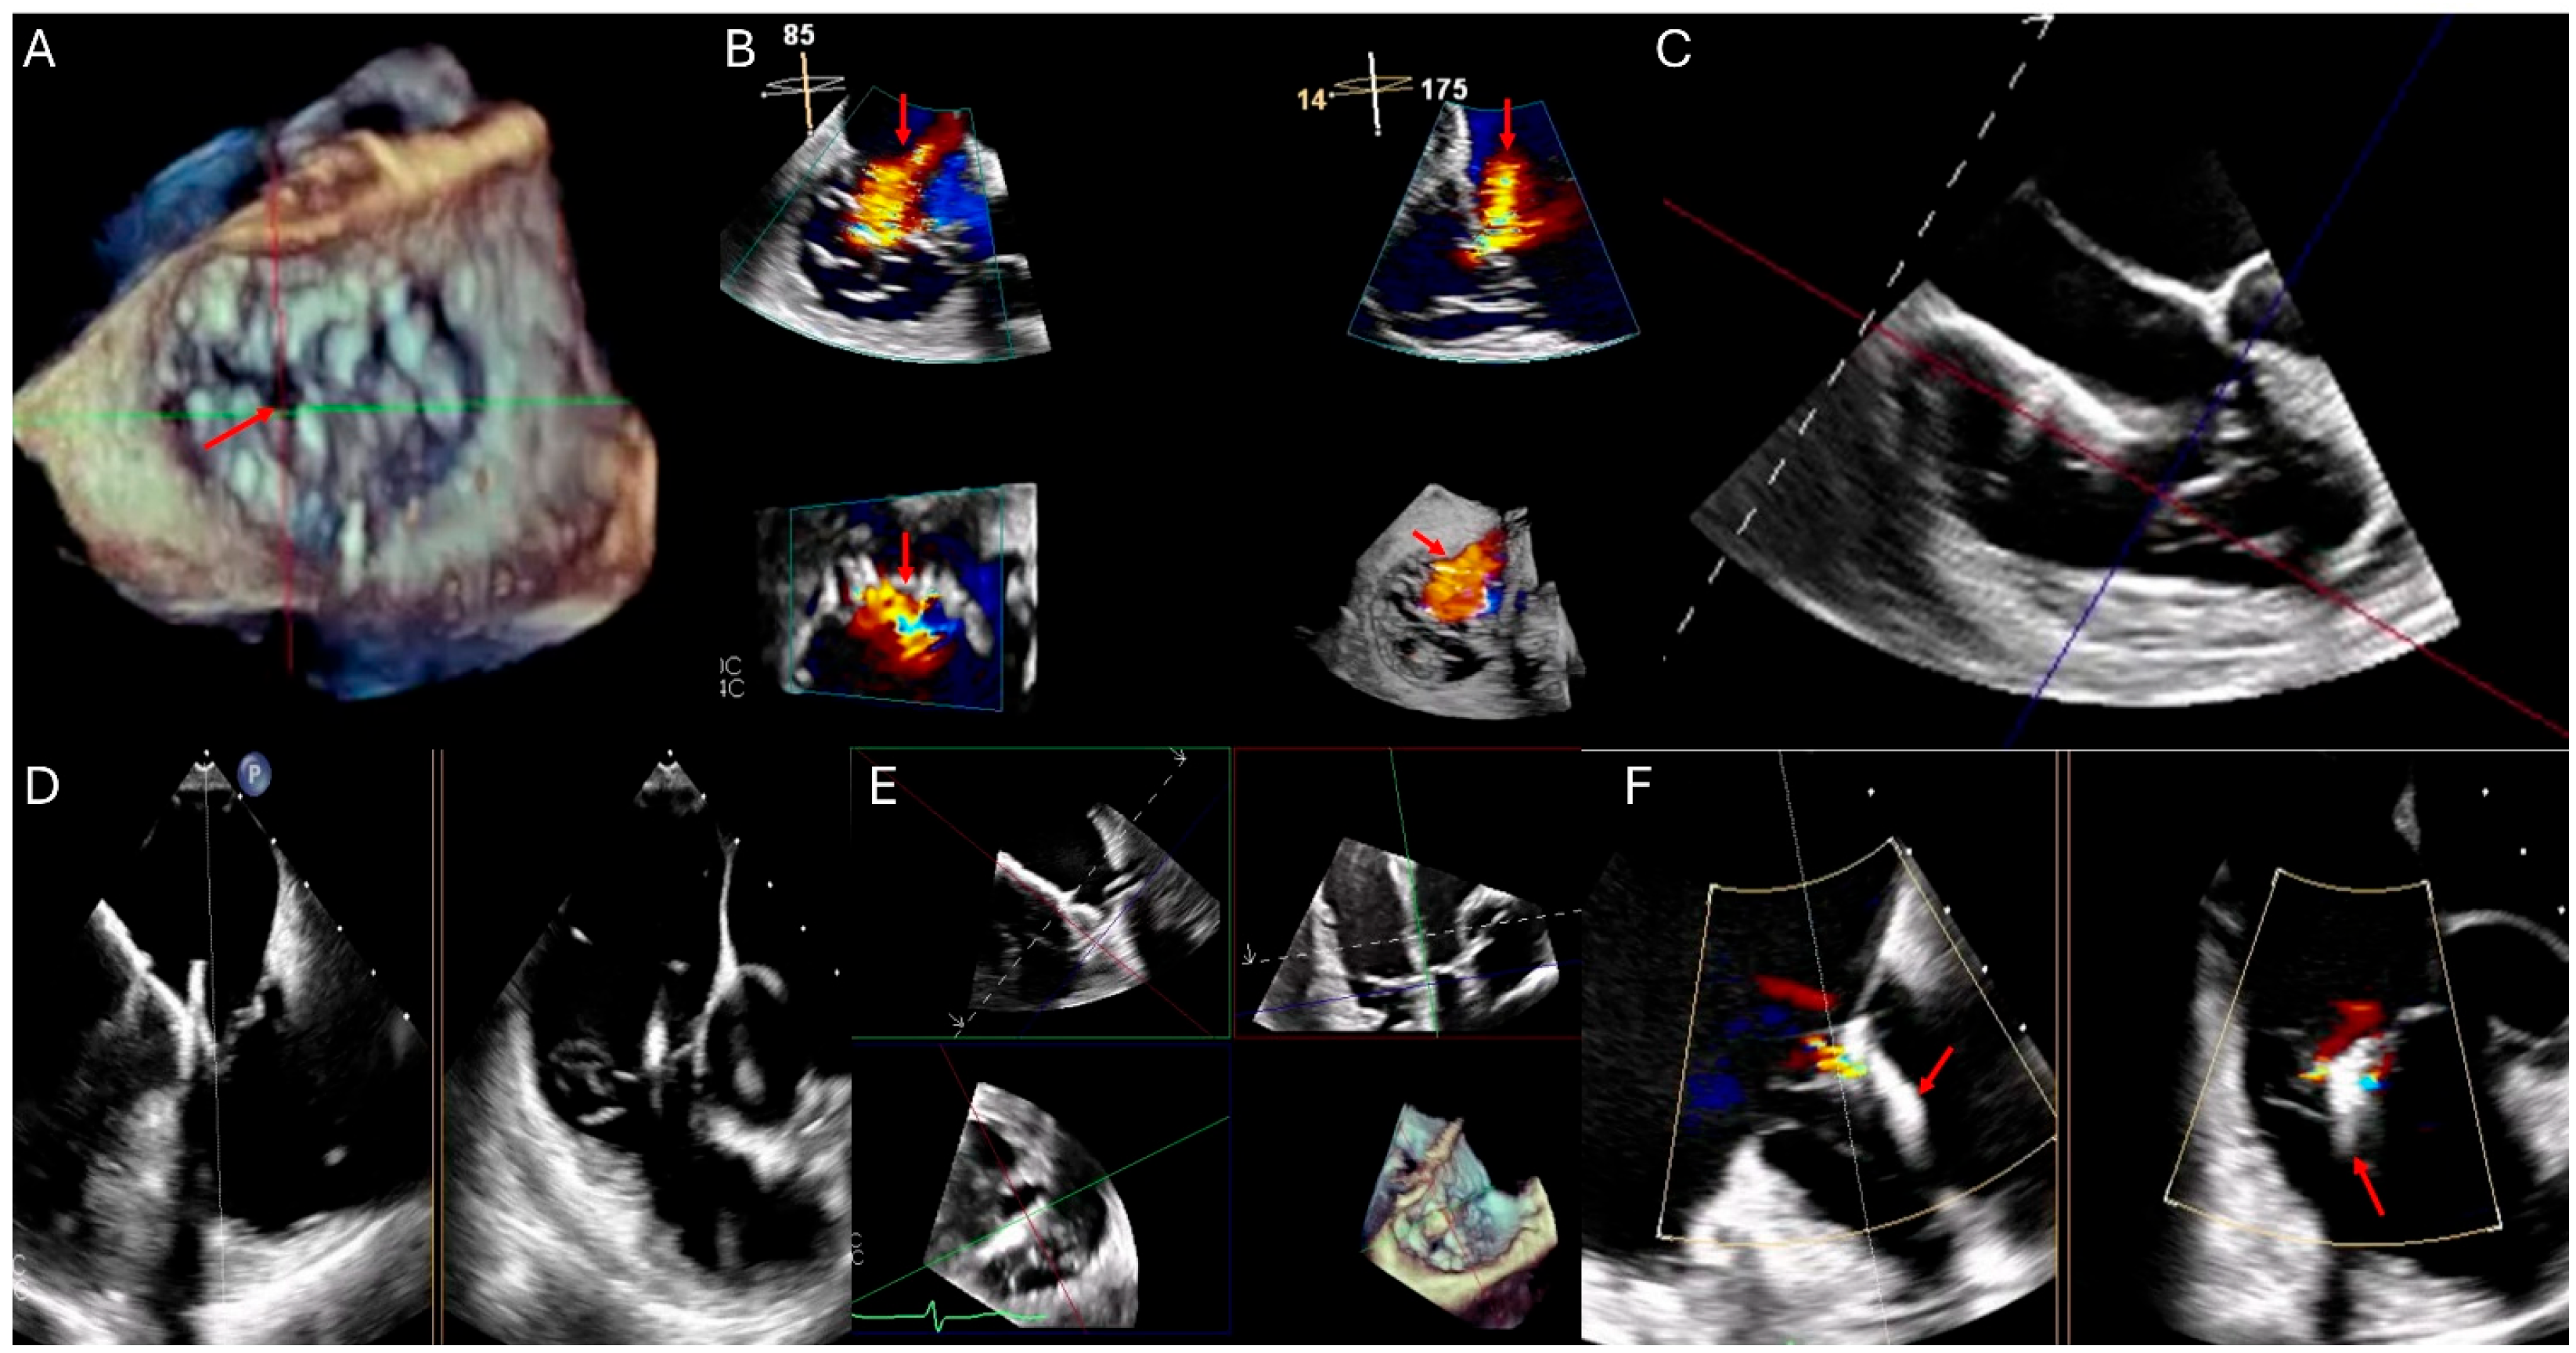

Figure 1—Echocardiographic qualitative and quantitative measures of TR.

In the echocardiographic assessment of TR, various qualitative, semi-quantitative, and quantitative parameters are used to classify the severity into mild, moderate, and severe categories. Qualitatively, TV morphology can range from mildly abnormal leaflets, such as mild rheumatic thickening or limited prolapse in mild cases, to severe valve lesions like flail leaflets, ruptured papillary muscles, severe retraction, or large perforations in severe TR [22]. Interventricular septal motion and characteristics of the flow convergence zone and the TR jet’s continuous wave (CW) Doppler signal vary significantly, from minimal abnormalities in mild cases to extensive changes in severe TR (Figure 1). Semi-quantitatively, the inferior vena cava (IVC) diameter, color flow jet area, vena contracta width, and proximal iso-velocity surface area (PISA) radius provide insights into the regurgitant flow, with all parameters increasing significantly as the severity progresses [22].

Quantitative measures such as the effective regurgitant orifice area (EROA) and regurgitant volume by PISA and 3D techniques further delineate the severity, with values escalating from less than 20 mm2 and under 30 mL in mild cases to more than 40 mm2 and over 75 mL in severe TR [22]. Hepatic vein flow and tricuspid inflow measurements complement these findings, helping to confirm the severity as indicated by systolic dominance in mild cases and systolic flow reversal in severe TR. These comprehensive assessments not only enhance the understanding of the pathological impact of TR but also guide clinical decision-making regarding the timing and type of therapeutic intervention needed [23,26] (Table 2).

Figure 1. Qualitative and quantitative parameters of severe tricuspid regurgitation (TR by echocardiography). (A) Apical four-chamber view showing right atrial (RA) and right ventricular (RV) dilation (asterisks). (B) Color Doppler highlights a large TR jet occupying > 50% of the RA. (C) Continuous-wave Doppler across the tricuspid valve reveals a dense, early peaking spectral Doppler profile (red arrow). (D) Zoomed view of the tricuspid valve shows a vena contracta width exceeding 7 mm (distance between tips of red arrows). (E) Proximal Isovelocity Surface Area (PISA) method demonstrates a large flow convergence zone (radius of 11 mm), with an effective regurgitant orifice area (EROA) ≥ 0.4 cm2. (F) Pulsed-wave Doppler of the hepatic veins shows systolic flow reversal (red arrow), a key marker of severe TR.